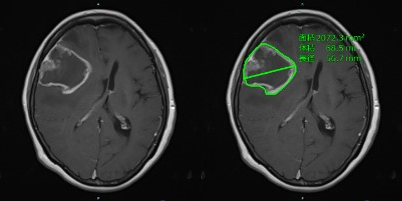

日本国立癌症研究中心联手日本富士胶片开发AI技术以提高神经胶质瘤图像评估的准确性

概述日本国立癌症研究中心和日本富士胶片株式会社已经共同开发了从MRI图像中精确提取神经胶质瘤数据的人工智能... -